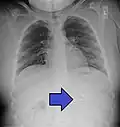

A coin seen on AP CXR in the esophagus -